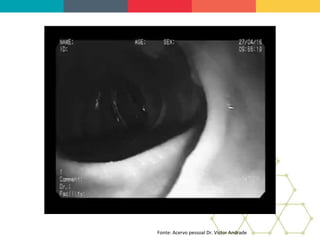

CONCLUSION: ERCP is a minimally invasive procedure

and choice in the treatment of bronchobiliary fistula with a

success rate close to 60%. The literature demonstrates

resolution of the fistula, with conservative treatments,

around five weeks. The patient progressed satisfactorily

with bilioptysis resolution and decrease the bilious flow

through the external abdominal drainage. A bronchoscopy

was performed after 15 days and did not show the

presence of bile secretion in the bronchial tree. In the

follow up of outpatient, didn't occurs any sign of

recurrence of the bronchobiliary fistula.

BRONCOSCOPIA